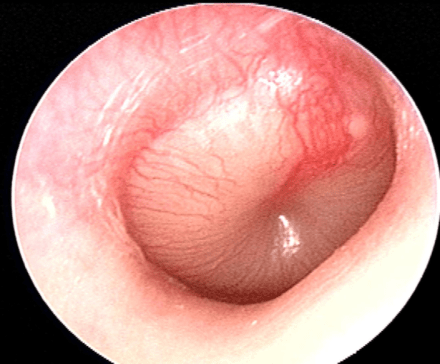

The diagnosis of AOM requires:

- Any of the above signs or symptoms; and

- Bulging of the TM, presence of middle ear effusion with inflammation, or TM hypomobility on pneumatic otoscopy